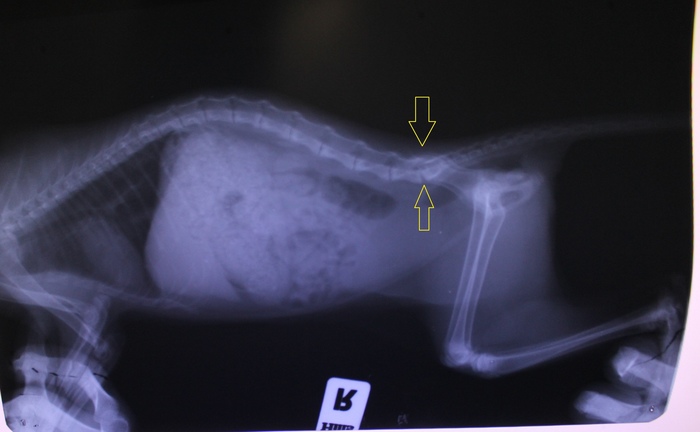

Мы с сестрой решили помочь денюжкой, пока могли. Собрали сумму, отнесли котёнка к ветеринару на рентген в одну клинику, врач сказал что перелома нет, только сильный ушиб. Лечения нам не назначили, сказали пройдет само.

Решились на второй заход к неврологу. Прогноз относительный. Мрт сделать не позволили финансы. Лапы чувствительность не потеряли.